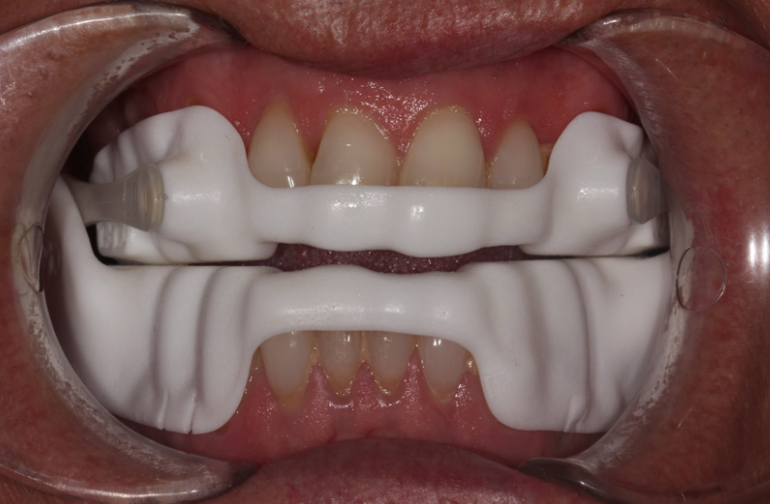

Digital impressions were captured using an intraoral scanner with CS 3600 acquisition software. This was critical because mandibular advancement devices require multiple bite registrations at different protrusion levels — something that digital scanning handles far more accurately than traditional impressions.

The software's undercut tools helped identify where tooth anatomy could be modified — for example, using direct composite attachments to create undercuts that improve appliance retention. Overjet and overbite measurements were recorded at the initial scan for comparison at future reviews to monitor any unwanted tooth movement.

The full arch scans were exported to ResMed, where the 3D model was aligned with a virtual articulator and the Narval CC appliance designed using a completely digital workflow — no physical models, no alginate, no stone.

On fitting day, the device was checked for retention, occlusion, TMJ comfort, connector mechanics, and protrusion accuracy. The fit was accurate and comfortable — reinforcing the benefits of a fully digital impression and design workflow over traditional methods.